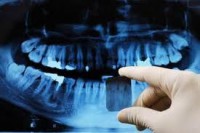

Contamos con apoyo Rx para cada una de las necesidades y especialidades, lo que permite lograr un diagnóstico certero, veraz y fidedigno.

Nuestro equipo radiológico es el siguiente:

- Equipos y Exámenes

- Radiografia Oclusal

- Radiografia Periapical

- Radiografía BiteWing o Aleta Mordida